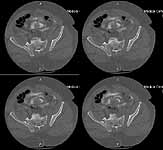

Five dayslater we was doing much better and was deemed fit for surgery. The site of his SP tube had completely healed up without evidence of infection. We took him to the OR to plate his symphysis, making our Pfannenstiel incision low to avoid the SP site. During plating we notice at one point some murky fluid in a little pocket deep inside his pelvis. The was sent for gram stain and culture and came back GPC and ultimately grew out enterococcus. We completed the symphseal plating & packed the wound with antibiotic beads. We brought him back at 48 hours for repeat I&D and removal of the beads and closure. He tolerated both of these surgeries well. About 5 days later(roughly 2 1/2weeks afterhis injury)his wound in the front was looking good and there was no evidence for infection. So he was brought back to the OR for posterior pelvic fixation. My plan had been to do an ORIF and place SI screws, but I couldn't get adequate inlet or lateral views. So we did an open reduction and posterior transiliac plating. The reductions in the front and the backwere difficult due to both his size and due to the time that had elapsed since his injury.I've enclosed pre and post xrays.